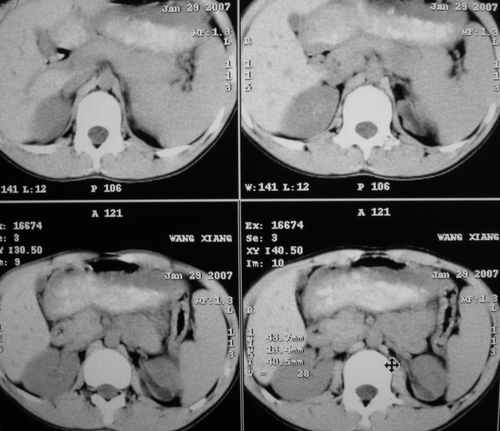

m 15y 外院b超发现左肾包块,遂来ct检查。

左肾外形明显小于右肾,左肾中上极后侧可见一等密度影,与肾分解不清,肾盂肾盏无扩张,先考虑:左肾发育不良,建议强化除外占位

左肾外形明显小于右肾,左肾中上极后侧可见一等低密度影,与肾分解不清,肾盂肾盏无扩张,先考虑:左肾发育不良,平滑肌脂肪瘤待排除。